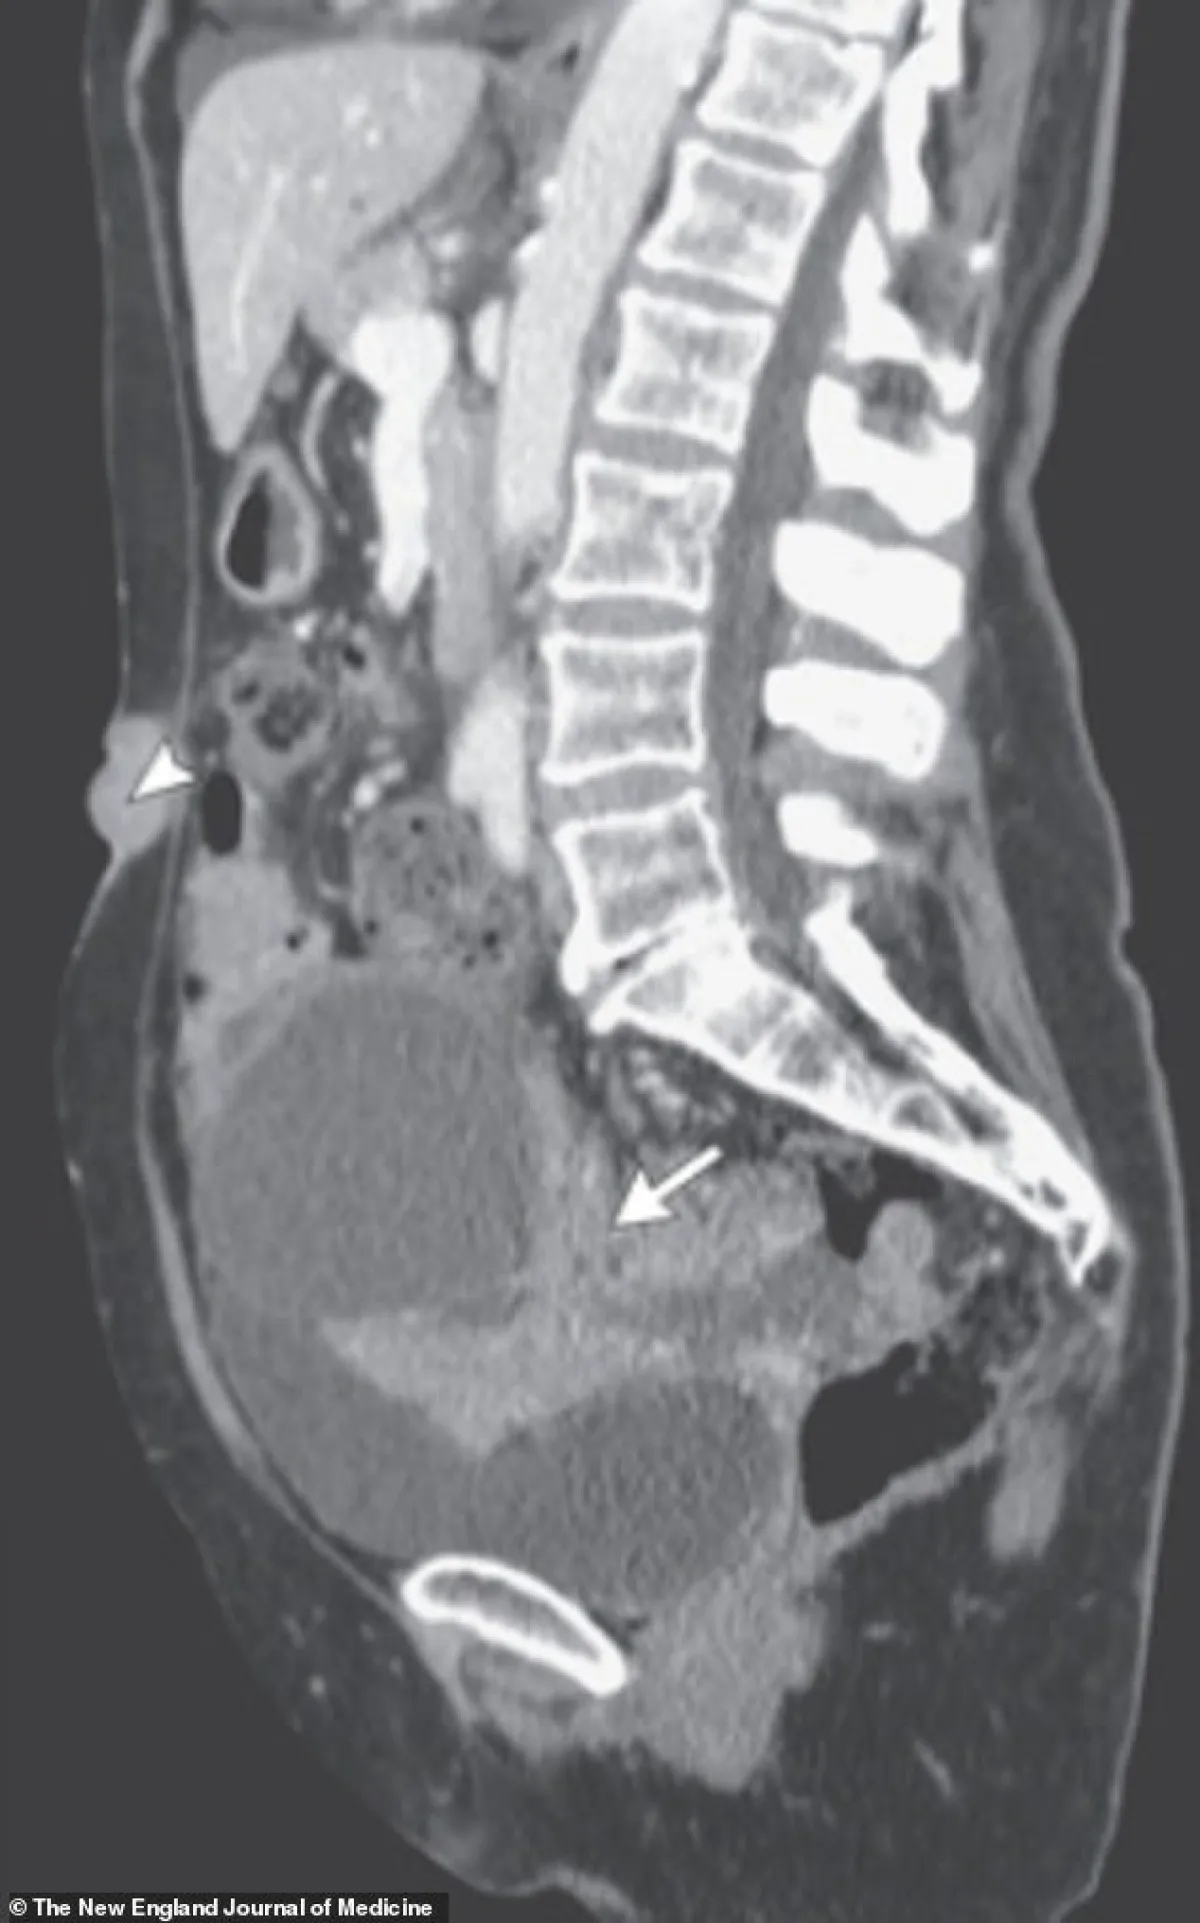

وجاء التحذير الطبي لفريق مستشفى جامعة خيمينيز دياز في مدريد ،بعد تشخيص امرأة تبلغ من العمر 73 عامًا بسرطان المبيض، بعد ظهور تورم في سُرتها على شكل كتلة حمراء صغيرة.

ويعرف سرطان المبيض باسم “القاتل الصامت”، لأنه يتم تشخيص نحو 80 في المئة من حالاته في المراحل المتقدمة من المرض، وفي وقت التشخيص، يكون بنسبة 60 في المائة من سرطانات المبيض قد انتشرت بالفعل إلى أجزاء أخرى من الجسم، مما يخفض معدل البقاء على قيد الحياة لمدة خمس سنوات.